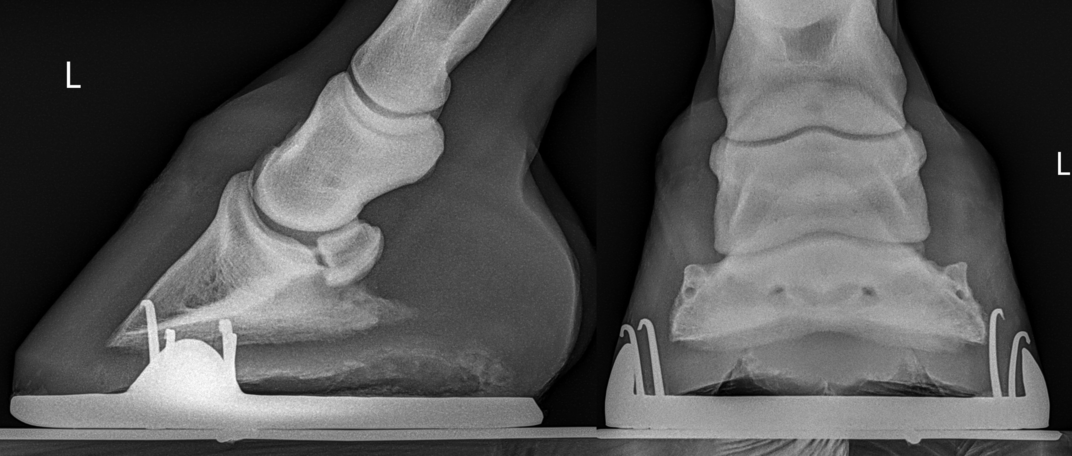

A real-world case example (educational)

In one case, a horse presented with a long-standing history of consistent soreness after trimming, described by the owner as “normal for him.”

On examination:

- Mild foot sensitivity was noted

- Digital pulses were slightly elevated after walking

- No acute laminitis was present

Because of the history and subtle exam findings, metabolic blood testing was pursued. Insulin values were found to be elevated, supporting a diagnosis of insulin dysregulation consistent with equine metabolic disease.

Identifying this allowed the care team to address the underlying metabolic contribution, rather than focusing solely on trimming mechanics.